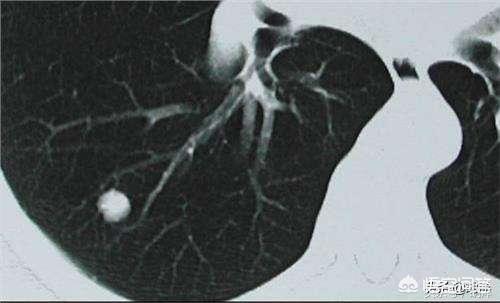

肺結節とは、肺にできる3cm以下の球状の病変のことで、胸部CTが健康診断に普及したことで、肺結節の発見率はどんどん高くなっており、違和感なく肺結節の検査を受けている人も多く、ネット上では「肺がんが怖い」と言われていますが、では結節の大きさはどれくらいなのでしょうか?

私たちはこの病気の診断の考え方を知っており、それから頭に戻って肺結節の話をする。肺結節とは、肺にできる直径3cm以下の円形または不規則な病変のことで、画像上では密度が増加した陰影として現れ、均質または不均一、単発または多発、境界が明瞭または不明瞭である。

肺結節の定義について、中国医学ガイドラインは次のように述べている:画像診断(胸部CT)により、直径3cm以下の限局性、円形状、密度増加した固形または亜固形の肺影が認められ、孤立性または多発性の可能性があり、肺無気肺、肺門リンパ節腫大、胸水を伴わない。

一般に、肺にできる直径3cm以下の密度増加影を肺結節と呼びますが、その危険度は大きさだけでなく、結節の形態、密度、増殖速度も合わせて判断する必要があります。

CT検査以前は、肺結節が発見される確率は0.2%以下であり、発見される結節の大きさは基本的に1cm以上であったが、CT検査の普及に伴い、肺結節が発見される確率は飛躍的に上昇したが、どの程度の大きさの肺結節であれば、あるいはどのような肺結節であれば、より危険なのかが、現在特に関心の高いテーマである。

第一に、肺結節の区分については、現在、8mm以上3cm以下の肺結節を典型的な肺結節と呼び、8mm未満の肺結節のみを小結節と呼んでいる!

第二に、肺結節の大きさと良性・悪性のリスクの程度には相関関係がある!一般的に、5mm未満の肺結節が悪性である確率は0~1%、5~10mmが悪性である確率は6~28%、20mm以上が悪性である確率はかなり高く、ほぼ60%以上と考えられており、これはすりガラス状の肺結節の悪性の程度と同様である!